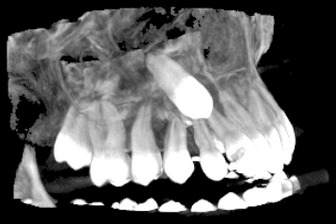

3D скенер на зъби – сектор

Чрез използването на модерната CBCT технология (Cone Beam Computer Tomography) се сканира триизмерен образ на част от челюстта, обхващаща до четири зъба. Този образ може лесно да се обработва. Разглеждането на структурата в 3-те различни равнини помага за прецизната диагностика. Изследването е подходящо за диагностициране на заболявания на зъбите, при ендодонтско лечение, както и за поставяне на единични импланти и др.